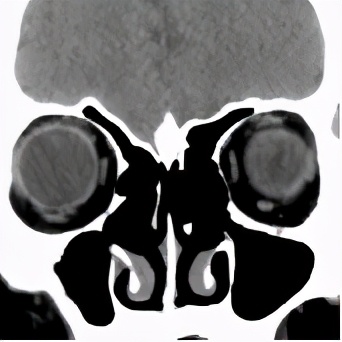

术前CT显示右侧鼻腔鼻窦密度增高,术后CT显示双侧鼻窦正常